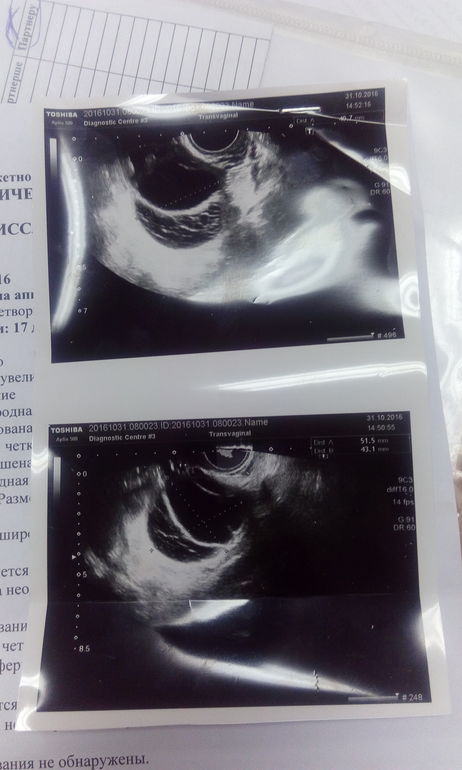

В ноябре планируем вступать в протокол, теперь переживаю что киста желтого тела не рассосется! Что делать чтобы она ушла? Что попить? Врачу не звонила не сообщала, но она мне до этого назначала пить прогинову с 21 дц по 2 таблетки 7 дней, дабы мои фолликулы были равномерные. Так хочется уже вступить в протокол. Вот картина